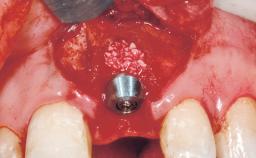

A 30-year-old female patient had lost tooth 21 and was referred to our clinic for consultation and treatment. Due to advanced apical infection, tooth 21 had been extracted two months earlier at another clinic and an acrylic-resin tooth had been bonded to the adjacent teeth. The patient desired implant treatment to avoid any damage to the adjacent natural teeth. While the patient had no history of any systemic disorder, she was a heavy smoker and exhibited medium to advanced periodontitis in the entire jaw. After the initial treatment to achieve a pocket probing depth of less than 4 mm and no bleeding on probing, a decrease in the height of the papillae mesial and distal to the extraction site and overall gingival recession were observed.

Bone Augmentation Horizontal|Staged

Augmentation Materials Autogenous chips|Membrane

Bone Volume Deficient horizontally, requiring prior grafting